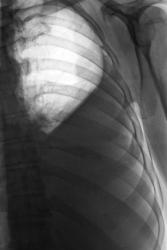

Правосторонний экссудативный плеврит.

До и после пункции.